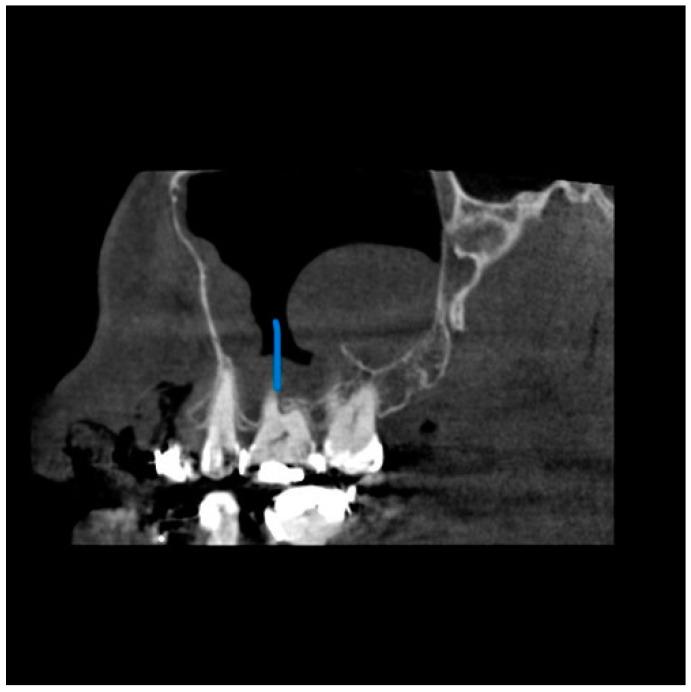

尽管锥形束计算机断层扫描(CBCT)在区分软组织方面存在局限性,但它对牙科手术产生了重大影响,并给我们的诊断和治疗计划方法带来了重大变革。它是一种出色的成像方式,能快速识别鼻窦混浊,并为鼻旁窦病变提供有价值的见解,且辐射暴露量低得多。本研究旨在调查CBCT扫描中上颌窦异常的发生率,确定这些发现的频率、类型和位置,并找出根尖周病变距离与上颌窦影像学变化之间的相关性。两名检查人员独立评估了117例患者,以诊断并将病例分类为不同的异常亚型。记录与鼻窦关系最密切的根尖周病变。记录左右上颌窦口的直径以及窦口下缘至鼻窦骨底的距离。将这些发现与这些患者的年龄和性别相关联。本研究表明,61例患者被诊断为黏膜增厚(52.1%)。受黏膜增厚影响最大的鼻窦壁是上颌窦底,其次是内侧壁和外侧壁。在19例有根尖周病变的患者中,15例有上颌窦黏膜增厚,这具有统计学意义(P = 0.004)。上颌窦异常的高发生率强调了放射科医生全面解读CBCT图像中获取的整个容积(包括整个鼻窦)的重要性。偶然发现可在个体的症状和体征临床背景中予以考虑,以降低高估影像学发现实际影响的风险。

https://cdn.ncbi.nlm.nih.gov/pmc/blobs/9100/10528184/82c09e24bc97/diagnostics-13-02918-g002.jpg